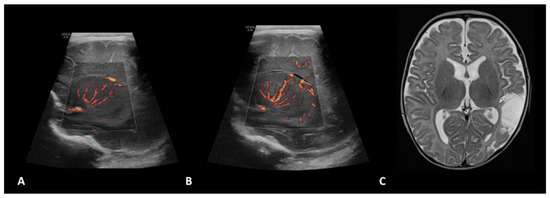

- Hwang, M.; Haddad, S.; Tierradentro-Garcia, L.O.; Alves, C.A.; Taylor, G.A.; Darge, K. Current understanding and future potential applications of cerebral microvascular imaging in infants. Br. J. Radiol. 2022, 95, 20211051. [Google Scholar] [CrossRef] [PubMed]

- Svrckova, P.; Meshaka, R.; Holtrup, M.; Aramburo, A.; Mankad, K.; Kazmi, F.; Owens, C.M.; Gala-Peralta, S.; Semple, T. Imaging of cerebral complications of extracorporeal membrane oxygenation in infants with congenital heart disease—Ultrasound with multimodality correlation. Pediatr. Radiol. 2020, 50, 997–1009. [Google Scholar] [CrossRef] [PubMed]

- Lyo, S.; Tierradentro-Garcia, L.O.; Viaene, A.N.; Hwang, M. High-resolution neurosonographic examination of the lenticulostriate vessels in neonates with hypoxic-ischemic encephalopathy. Br. J. Radiol. 2022, 95, 20211141. [Google Scholar] [CrossRef] [PubMed]